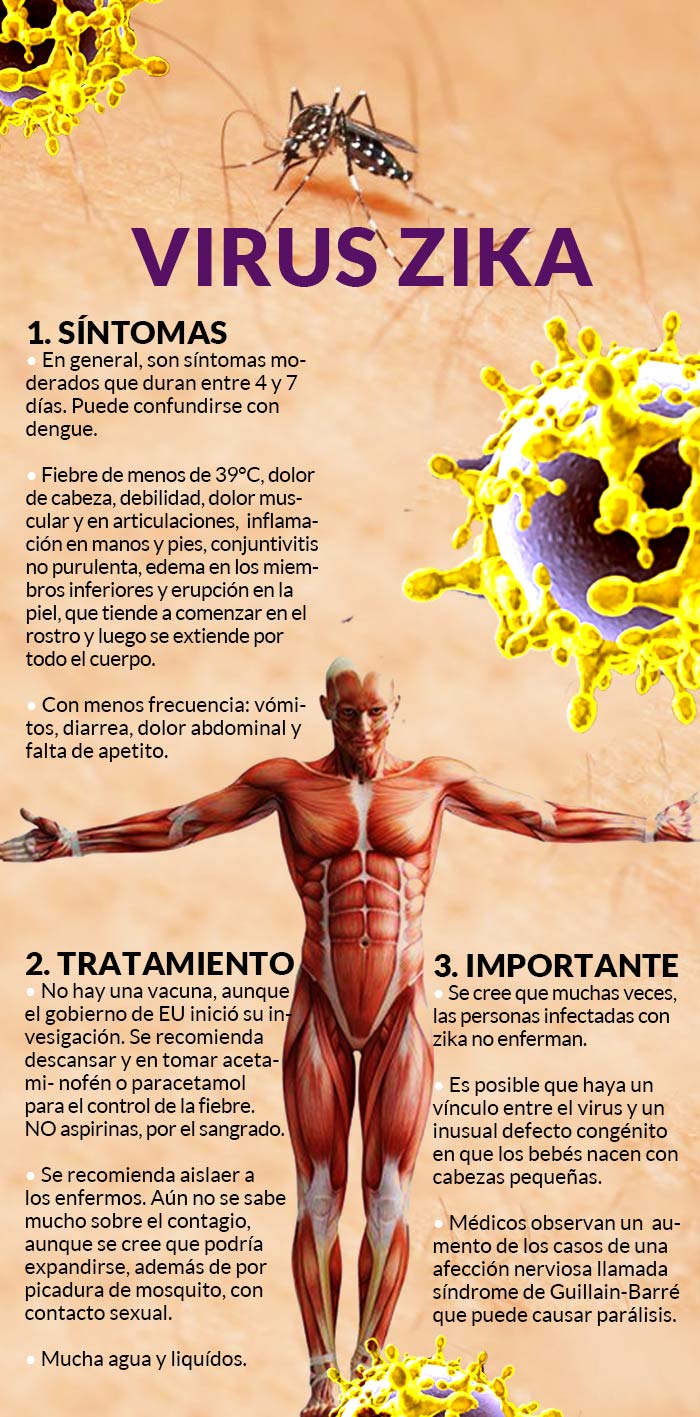

El zika es una rara enfermedad tropical transmitida a los humanos por mosquitos. Produce por lo general afecciones leves, pero ahora hay sospechas de que esté relacionado con una malformación congénita y posiblemente otros problemas de salud. La Organización Mundial de la Salud (OMS) declaró que es posible que haya un vínculo entre el virus y un inusual defecto congénito en que los bebés nacen con cabezas pequeñas, pero aclaró que hasta ahora la evidencia ha sido circunstancial.

El gobierno de Estados Unidos comenzó la investigación para una posible vacuna. Pero el desarrollo de una vacuna generalmente toma varios años, por lo que no se debe esperar una solución en el futuro cercano. “No será de la noche a la mañana”, dijo el martes en una entrevista el doctor Anthony Fauci de los Institutos Nacionales de Salud.

• El zika se transmite mediante picaduras de la misma clase de mosquitos que pueden propagar otras enfermedades tropicales, como el dengue, el chikungunya y la fiebre amarilla. No se conocen casos de transmisión de persona a persona.

• Los expertos creen que la mayoría de las personas infectadas con el virus zika no enferman. Y quienes enferman normalmente desarrollan síntomas leves, fiebre, sarpullido, dolor en las articulaciones y enrojecimiento de los ojos, que por lo general no duran más de una semana. No existe un medicamento específico y no se desarrollado una vacuna contra él, a diferencia de algunas enfermedades tropicales que aparecen en brotes periódicos.

En Brasil han aumentado las pruebas que vinculan la infección del zika en mujeres embarazadas al nacimiento de niños con una rara malformación congénita llamada microcefalia, y que hace que el bebé nazca con la cabeza más pequeña de lo normal y sin que el cerebro se haya desarrollado correctamente.

Los médicos han observado un aumento de los casos de una afección nerviosa llamada síndrome de Guillain-Barré que puede causar parálisis. Sin embargo, no está clara la relación con el virus zika. Otras infecciones pueden desencadenar el mal, como el dengue.